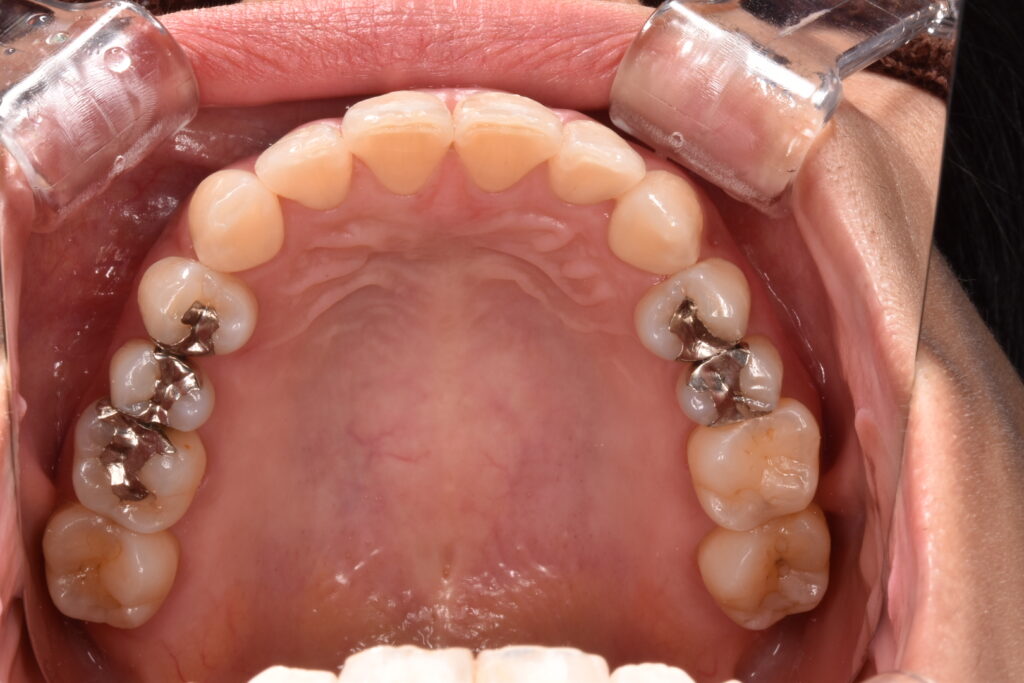

40代女性 他院でマウスピース矯正をされた後、当院で銀歯のやりかえをご相談くださいました。やりかえ希望は上の歯で5本、下の歯で1本です。

治療前後